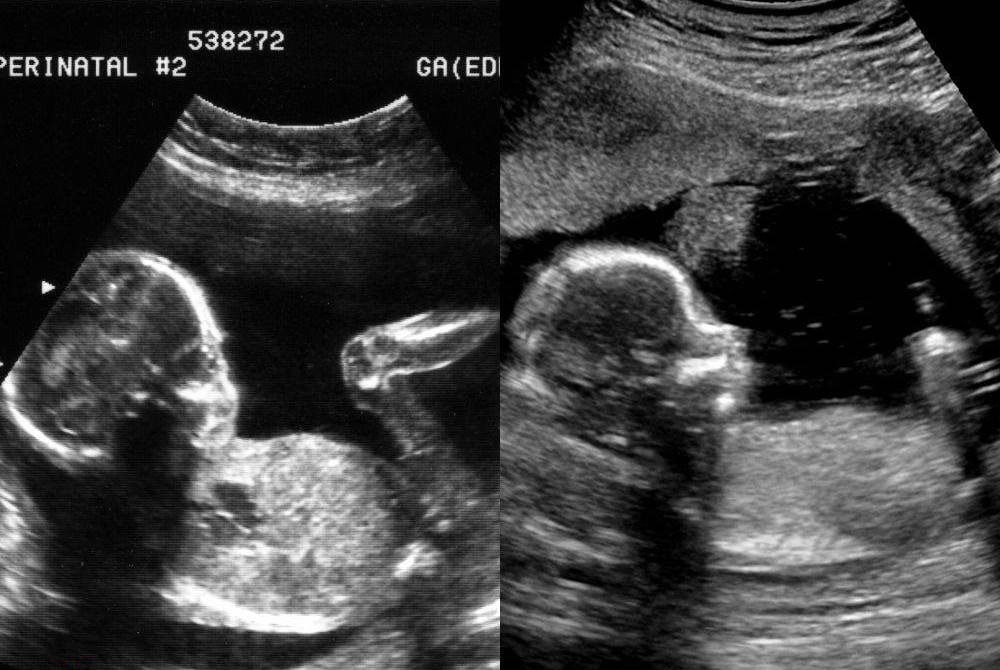

Welches von beiden wurde bei einer Vergewaltigung gezeugt?

05. Juni 2020 · Standpunkte

Neulich haben wir bei sundaysforlife zwei Ultraschallbilder nebeneinander gepostet. Über den Bildern stand: „Welches von beiden wurde bei einer Vergewaltigung g…